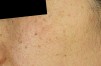

주근깨/흑자(표재성 색소)

표재성 색소란?

주근깨와 흑자는 피부에 나타나는 대표적인 색소 병변으로, 자외선 노출과 유전적 요인이 주요 원인입니다.

주근깨 (Freckles)

• 1주로 10~20대에서 나타나는 표재성 색소 병변으로, 피부 표피층에 위치합니다.

• 2선천적 요인이 강하며, 경계가 뚜렷하고 작은 갈색 점 형태로 나타납니다.

흑자(Lentigo)

• 120~30대 초반에는 표재성 색소로 분류되는 경우가 많으며, 경계가 명확하고 주근깨보다 크고 진한 갈색을 띱니다.

• 2그러나 연령이 높아질수록 진피형 흑자의 가능성이 커지며, 특히 40대 이상이나 출산 후 여성에게서 흔히 나타납니다.

• 3진피형 흑자는 경계가 불분명하고 옅은 갈색 또는 회갈색으로 보이며, 치료가 더 까다로울 수 있습니다.